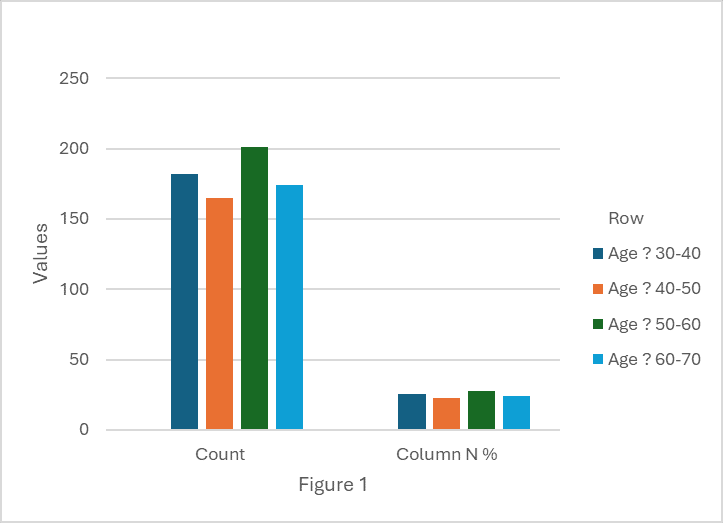

Key Predictors of Intraoperative and Postoperative Complications in Laparoscopic Cholecystectomy: Insights From a Jordanian Cross-Sectional Study

Aim: This is the first study in Jordan that investigates the main demographic and health characteristics that determine the form...Read More